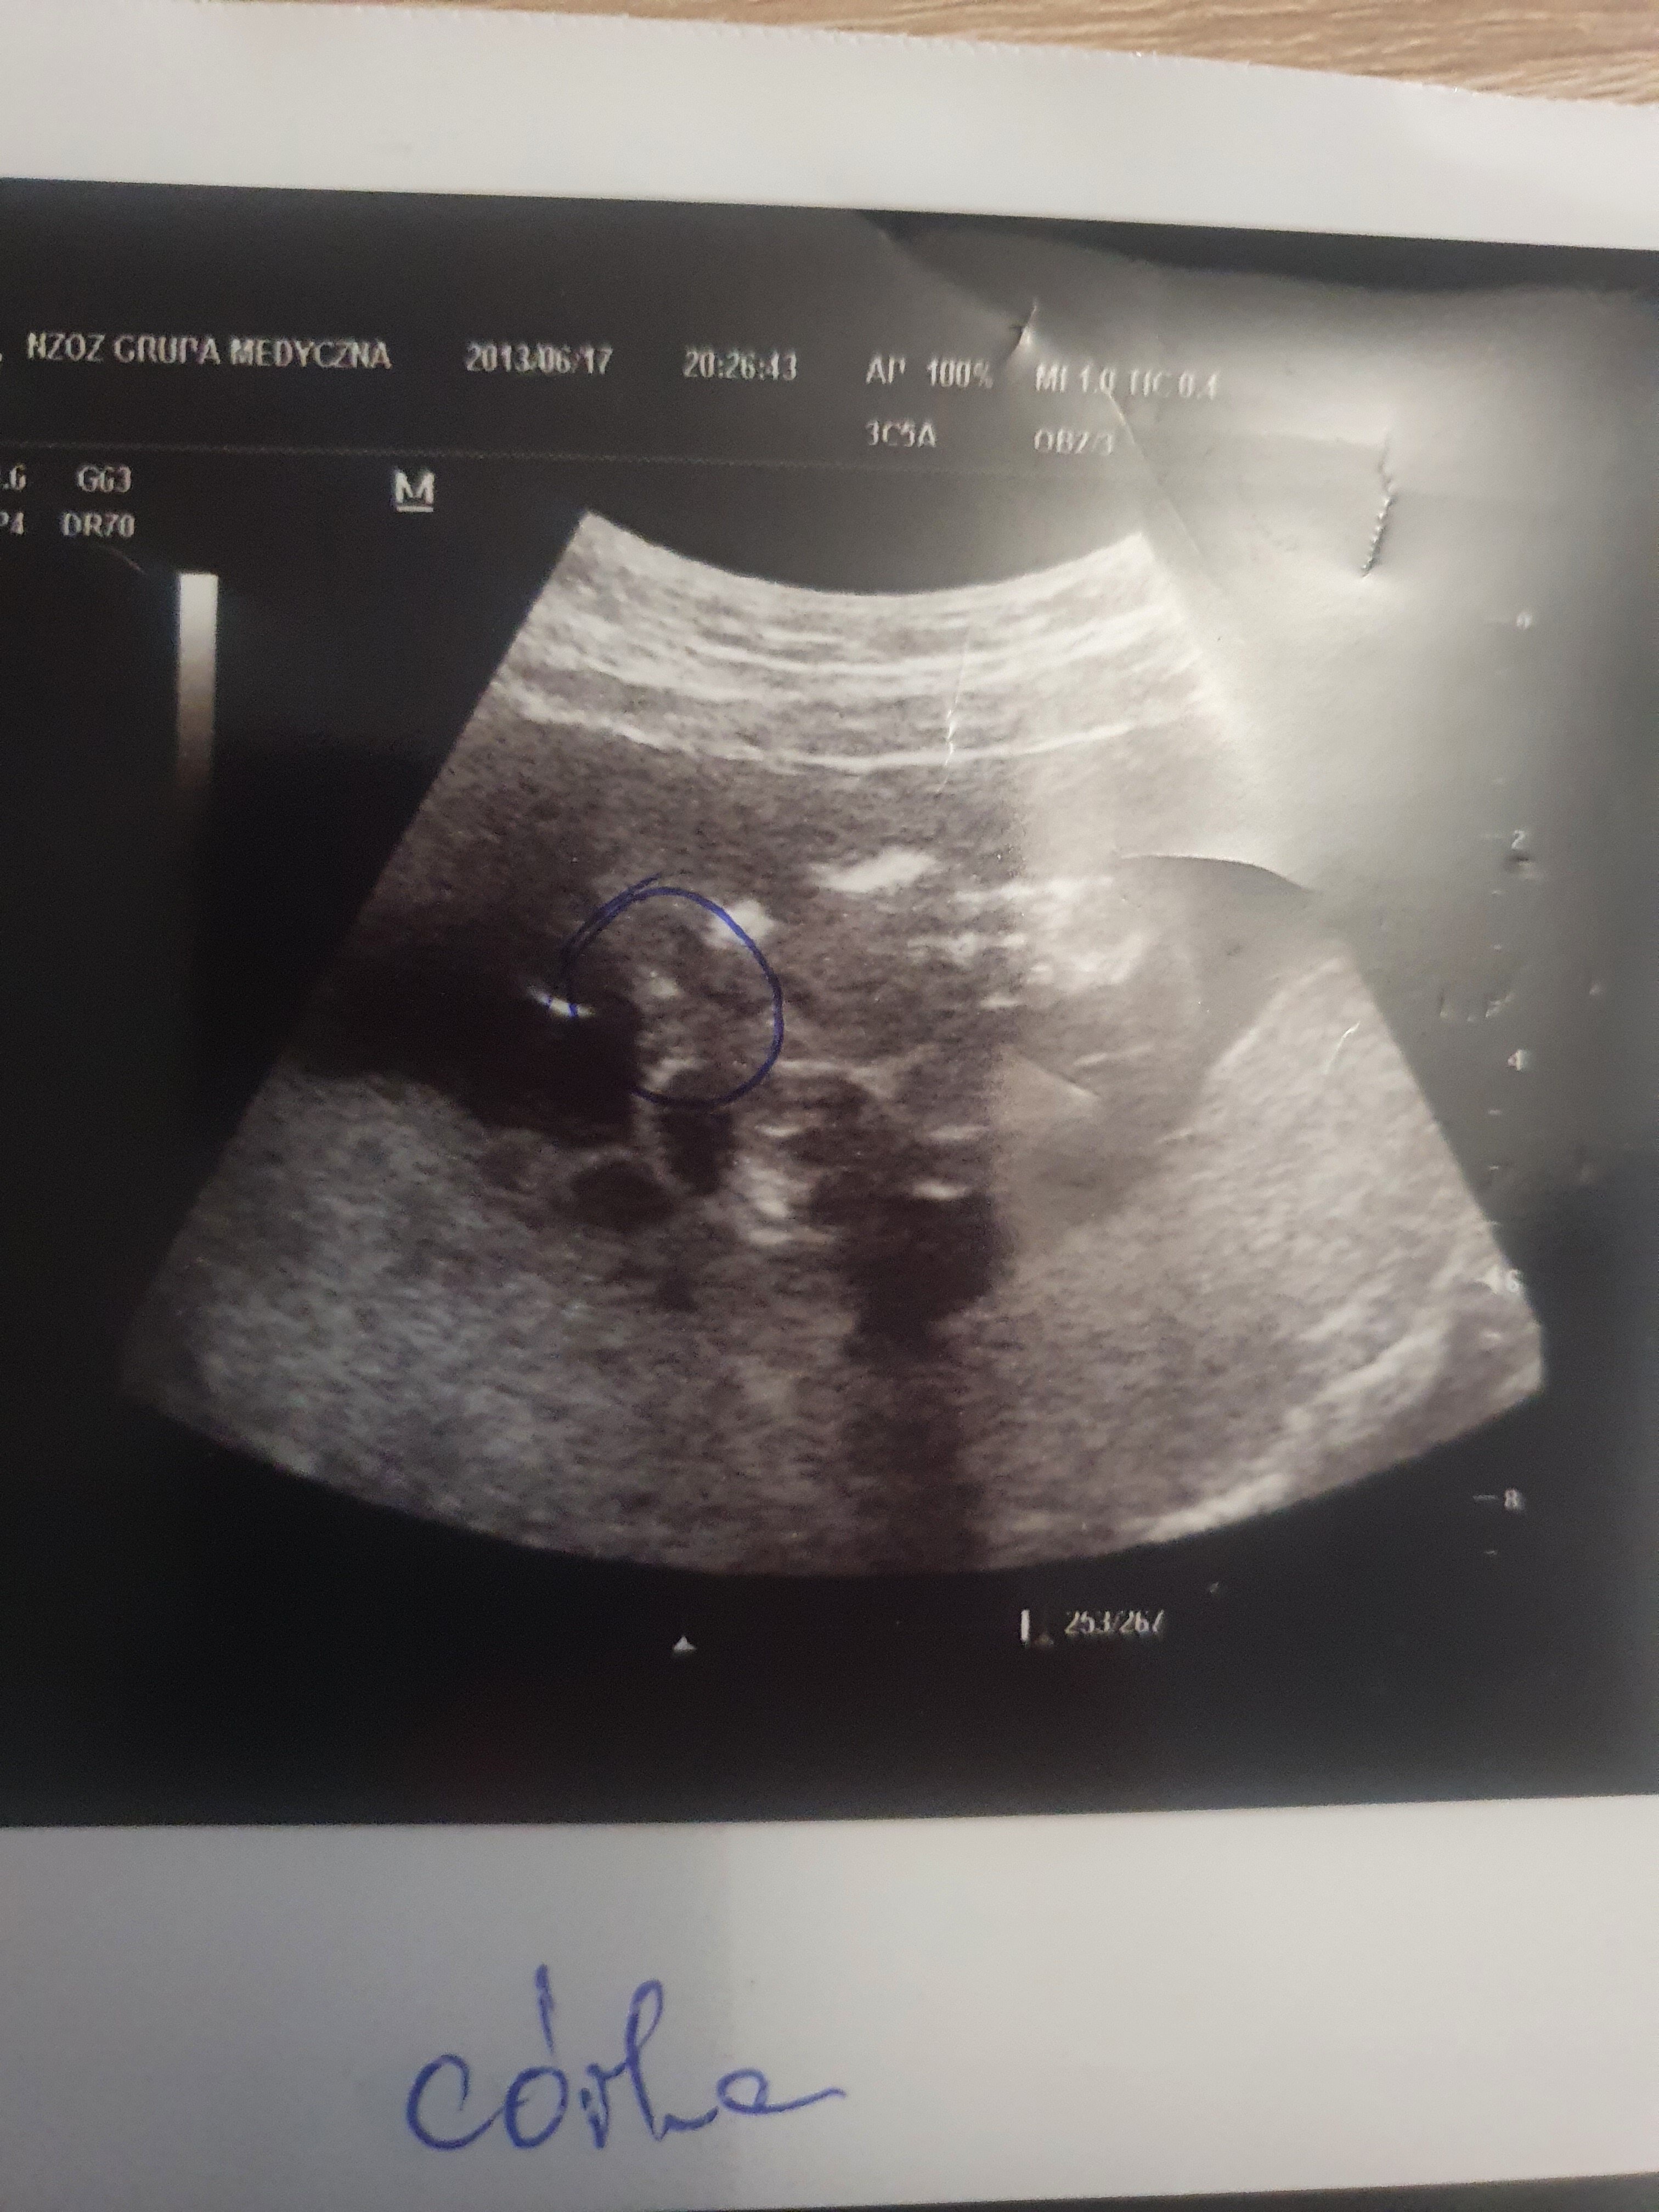

Mam tylko corke wiec nie mam porownania w usg dodam zdjecie corki 8 lat temu wygladalo to zupelnie inaczej i dla. Mnie bylo jasne w dodatku zaznaczyl i napisal ze napewno cora.. A tu kupe kasy wydane i ja nie jestem pewna w stu procentach po jej wypowiedziach dr byla z polecania kolezanki i dodam ze tania to nie byla bo az 370zl skasowala za samo usg ps w zalaczniku zdjecie starszej corki

• 20220530_193055.jpg

20220530_193055.jpg

1,4 MB · Wyświetleń: 525